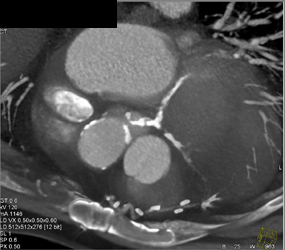

Diagnosis

Normal RCA